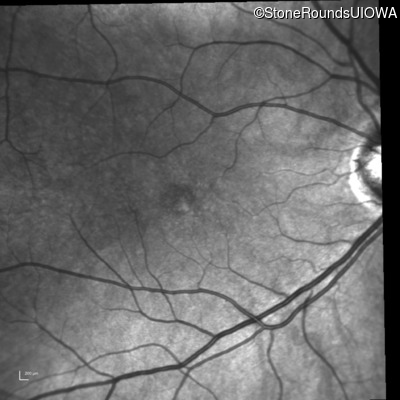

Fluorescein Angiography - Left - 20/40

Exemplar